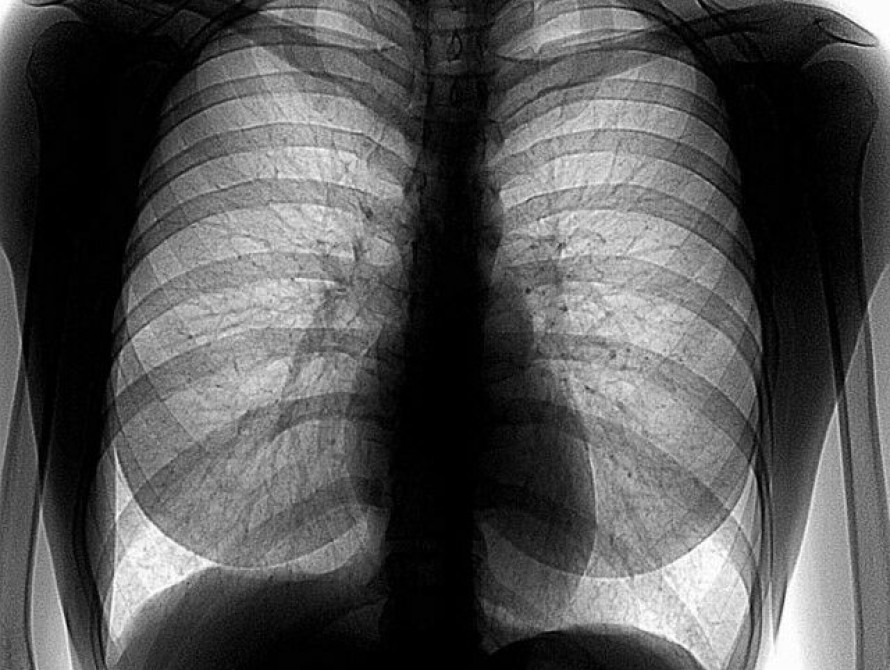

В Запорожье на территории Свято-Покровского архиерейского собора с 8.00 до 14.00 все желающие могут бесплатно пройти флюорографию.

Как сообщили "ZaБору" сегодня, 15 марта, в пресс-службе запорожской епархии, услугой могут воспользоваться абсолютно все, включая неимущих граждан и лиц без определенного места жительства. Услуга проводится в специализированном переездном кабинете медицинской рентгендиагностики.